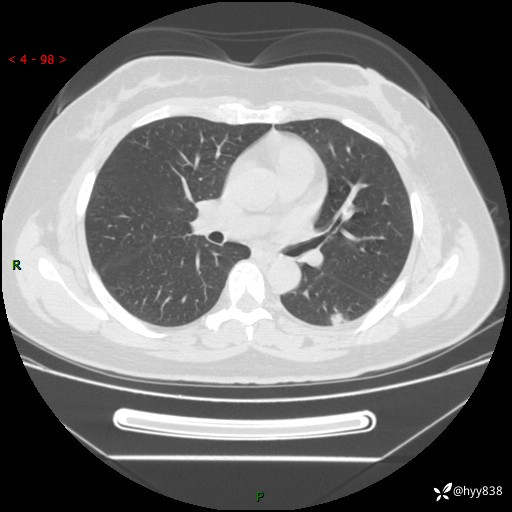

胸部CT复查+增强(2024.6)